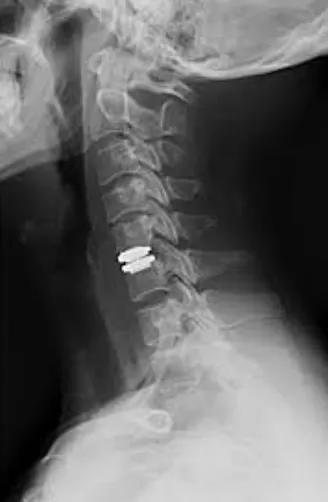

椎間盤置換術:透過手術置換成人工椎間盤。